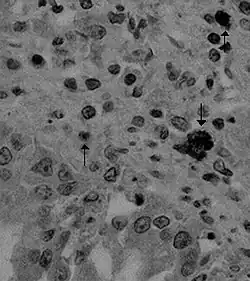

| Canine coronavirus antigen (arrows) in canine lung tissue | |